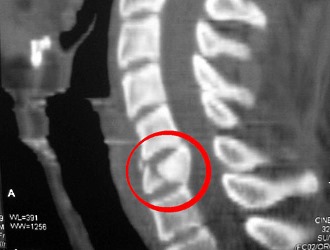

Диагностика

После травмы необходимо обратиться к травматологу или хирургу. Врач проведет обследование, чтобы определить расположение ушиба, степень повреждения и характер травмы. Сначала он опросит пациента о жалобах и причинах травмы, затем пальпирует поражённую область. Для оценки рефлексов сухожилий и характера болей может потребоваться консультация невропатолога. Пациента направляют на рентгенографию позвоночника для оценки тяжести ушиба. Если возникают сомнения в диагнозе, назначают компьютерную томографию. Перед назначением лечения врач может направить на биохимический анализ крови для выбора наиболее эффективного препарата или метода терапии.

Для исключения перелома позвоночника назначают рентгенографию. В сомнительных случаях дополнительно проводят КТ или МРТ. При подозрении на неврологические нарушения пациента направляют к невропатологу или нейрохирургу. Лечение осуществляет врач-травматолог в травмпункте. Рекомендуется постельный режим. Для разгрузки позвоночника лучше спать на жесткой поверхности (можно подложить деревянный щит под матрас) с валиком под поясницей.